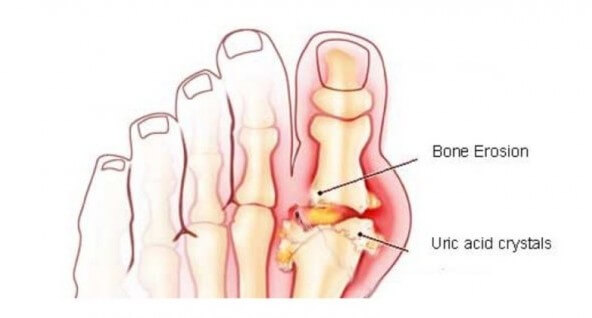

과다한 요산의 가장 주요한 증상은 관절, 특히 엄지발가락의 뻣뻣함, 붓기, 통증이다. 그리고 요산 수치가 아주 높아지면 “통풍”으로 알려진 질환을 촉발할 수 있다. 오늘 이 글에서요산과 통풍을 위한 자연 치료법을 함께 알아보자.

요산은 몸이 퓨린에서 생성한 노폐물로, 섭취한 음식(특히 육류)에서 나오는 것이다. 요산이 적정 수준일때는 신체의 정상적인 기능을 돕지만, 수치가 너무 높아지면 통풍을, 학명으로 “고뇨 산혈증”을 야기할 수 있다.

이 질환이 생기면 관절에 결정의 일종이 형성되어 관절염을 유발하며, 요산 수치가 높은 사람들은 신장 결석도 자주 생긴다. 다시 말해서, 요산은 신체 다양한 곳에서 형성되는 특정 침전물을 생기게 해 건강상 문제를 유발한다.